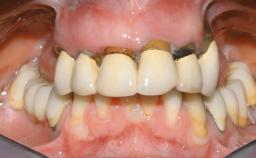

Immediate Loading of Six Implants in the Maxilla and Final Restoration with a Full-Arch CAD/CAM Zirconia FDP

A 63-year-old male patient was referred for a consultation and treatment of partial edentulism in the maxilla. The patient presented with residual anterior teeth and declined a partial removable prosthesis. He reported that the maxillary posterior teeth had been extracted due to mobility and periodontal disease two months before the consultation. The patient’s chief complaint was that his residual maxillary teeth were mobile and that he was unable to chew. The patient’s desire was a stable and comfortable fixed maxillary rehabilitation. The patient was a light smoker (fewer than 10 cigarettes/ day), and his medical history was without significant findings. He was not on any regular medication at the time of consultation. The extraoral examination revealed a normal physiognomy with a correct distribution of the facial thirds. The patient presented a low lip line, and the transition line between teeth and soft tissues was not exposed during a forced smile.

Prosthesis Type FDP

Defining Characteristics Fully edentulous upper jaw to be rehabilitated with an implant-borne fixed dental prosthesis